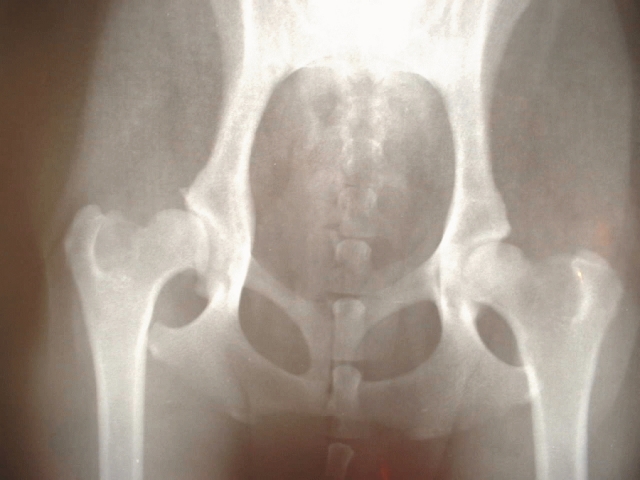

変形性股関節症 レントゲン所見による進行評価と見逃せないポイント

「変形性股関節症って、レントゲンで何がわかるの?」とよく聞かれます。答えのひとつが関節裂隙(れつげき)の狭小化です。ちょっと難しく聞こえるかもしれませんが、これは股関節のレントゲン写真を見たときに、太ももの骨(大腿骨)と骨盤側のくぼみ(臼蓋)の間にある“すき間”が、だんだん狭くなっていく現象のことを指します。

この「すき間」は、実際には軟骨の厚みです。レントゲンでは軟骨自体は映りませんが、骨と骨の間にある空間として見ることができます。つまり、裂隙が狭くなるというのは、「軟骨がすり減ってきている」と推測されるサインだと言われています(引用元:https://takeyachi-chiro.com/buttockpain/)。

変形性股関節症が進行すると、レントゲン写真にはいくつか特有のサインが見られるようになると言われています。その代表的なものが骨棘(こつきょく)、軟骨下硬化(なんこつかこうか)、そして**骨嚢胞(こつのうほう)**です。名前だけ聞くとちょっと難しく感じますが、それぞれがどんな変化なのか、できるだけわかりやすく説明していきますね。

「レントゲンで何か白っぽい突起があるって言われたんですけど…」という方、それが骨棘かもしれません。骨棘は、関節の端っこにできるとげ状の骨の突起で、軟骨がすり減ったり摩耗したあとに、関節の負担を少しでも軽くしようとして、体が自然に作り出すとも言われています(引用元:https://takeyachi-chiro.com/buttockpain/)。

軟骨のすぐ下にある骨が、摩擦や衝撃に耐えようとして硬く、そして密度が高くなることで、レントゲン上では白く濃く映るようになります。この状態は、軟骨が薄くなっている証拠とも言われていて、関節への負荷が続いているサインとも解釈されています。

「レントゲンで“穴がある”って言われてビックリしました…」という方もいるかもしれません。それが骨嚢胞です。これは、関節の衝撃や炎症などが影響して、骨の中に液体がたまった小さな袋状の空洞ができるものと考えられているそうです。